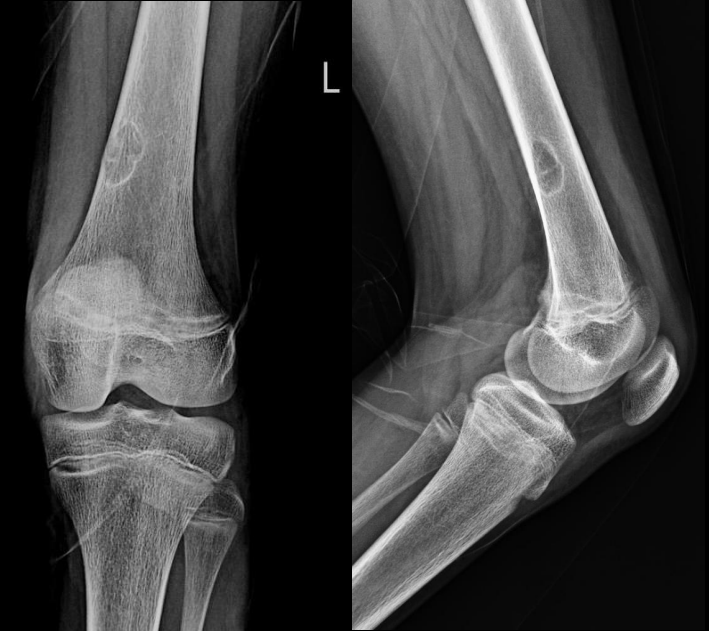

16 yo female, hurt her left knee while playing football

Views: AP and lateral left knee(0.33 point) Cortical-based eccentric metadiaphyseal lucent lesion with a sclerotic rim is seen at the posteromedial aspect of the lower left femur. (2 points)It shows overlying focal cortical thinning. No periosteal reaction, no cortical break through is seen.

The joint spaces are preserved. The soft tissues are unremarkable. The alignment is normal.

Impression: No radiographic evidence of fracture. (0.33 point) Fibrous xanthoma/non-ossifying fibroma (1point)

Management: Inform patient. Leave alone. (0.33 point) Skeletal leave alone lesions, also called “do not touch” lesions, are so characteristic radiographically, that further diagnostic tests such as a biopsy are unnecessary and can be frankly misleading and lead to additional unnecessary surgery. Thus a radiologic diagnosis should be made without a list of differential possibilities.